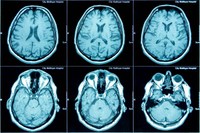

IRM cérébrale : indications, avec ou sans injection et interprétation

L’IRM cérébrale est un examen d’imagerie essentiel pour visualiser en détail le cerveau et ses structures. Elle est souvent prescrite pour explorer des symptômes neurologiques ou surveiller certaines pathologies. Dans cet article, nous vous expliquons pourquoi et comment se déroule une IRM cérébrale, les différences entre IRM avec et sans injection, sa durée, son coût, ainsi que la conduite à tenir en cas de résultats anormaux.

L’Imagerie par Résonance Magnétique (IRM) est un examen médical non invasif qui permet d’obtenir des images très précises du cerveau. Elle est prescrite dans de nombreux cas pour aider au diagnostic ou au suivi de maladies neurologiques.